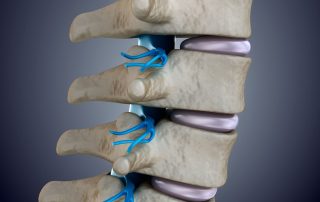

Minimal İnvaziv Omurga Cerrahisinin Temel Prensipleri Nelerdir?

Minimal invaziv omurga cerrahisi ne anlama gelir? Minimal invaziv omurga cerrahisi, kas ve kemik dokularını koruyarak yapılan kapalı cerrahi yaklaşımları ifade eder. Minimal invaziv cerrahi, kas ve kemik dokularını korumayı esas alır. Büyük kesiler yerine küçük girişler tercih edilir. Bu da iyileşme süresini kısaltır. Minimal invaziv omurga cerrahisi, omurgaya ulaşmak için klasik açık cerrahide görülen geniş kesiler ve yaygın doku ayrıştırmaları yerine, küçük girişlerle ve hedefe odaklı koridorlarla yapılan kapalı cerrahi yaklaşımları ifade eder. Buradaki “minimal” kelimesi, işlemin önemini küçültmez; hedef, omurga etrafındaki kas ve kemik dokularını mümkün olduğunca koruyarak aynı tedavi etkisini daha kontrollü bir şekilde elde etmektir. Bu [...]